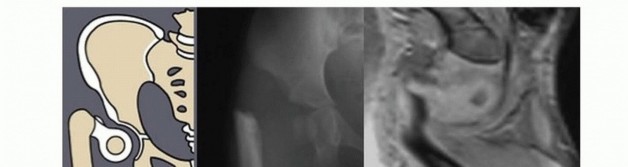

Illustration 3 for Treatment for Congenital Femoral Deficiency: What You Need to Know Illustration 4 for Treatment for Congenital Femoral Deficiency: What You Need to Know Illustration 5 for Treatment for Congenital Femoral Deficiency: What You Need to Know Illustration 6 for Treatment for Congenital Femoral Deficiency: What You Need to Know FIG 2 • A. Paley type 1b CFD (subtrochanteric type) shown by illustration, radiograph, and MRI. Note the nonossified subtrochanteric cartilage B. Paley type 1b CFD (neck type) shown by illustration, radiograph, and MRI. Note the nonossified neck. *

Other imaging studies that are useful include magnetic resonance imaging (MRI) and arthrography of the hips. All Paley types 1b and 2 should have an MRI after age 18 months to confirm whether there is a cartilaginous connection between the femoral head and shaft (

FIG 4 *).

Arthrography under general anesthesia is also helpful to determine the presence of pseudarthrosis versus delayed ossification of the proximal femur. Although the arthrogram is obtained, the lower extremity is manipulated and the proximal femur is visualized.

If the proximal femur and femoral head move as a unit, this usually denotes a cartilaginous connection

in the proximal femur, and the CFD is classified as type 1b. The arthrogram is also useful to differentiate between Paley types 2a and 2b. Both 2a and 2b might have a femoral head present; the difference is whether the femoral head is fused to the acetabulum or not. If dye can be injected into a joint space, the hip can usually be classified as type 2a. In some cases of type 2a, the dye can be seen to outline a cleft through the femoral neck. Illustration 8 for Treatment for Congenital Femoral Deficiency: What You Need to Know Illustration 9 for Treatment for Congenital Femoral Deficiency: What You Need to Know FIG 4 • MRIs of Paley type 2 CFD. The femoral head is clearly seen (A), and in a separate cut, one sees the proximal femur in a different plane (B). *